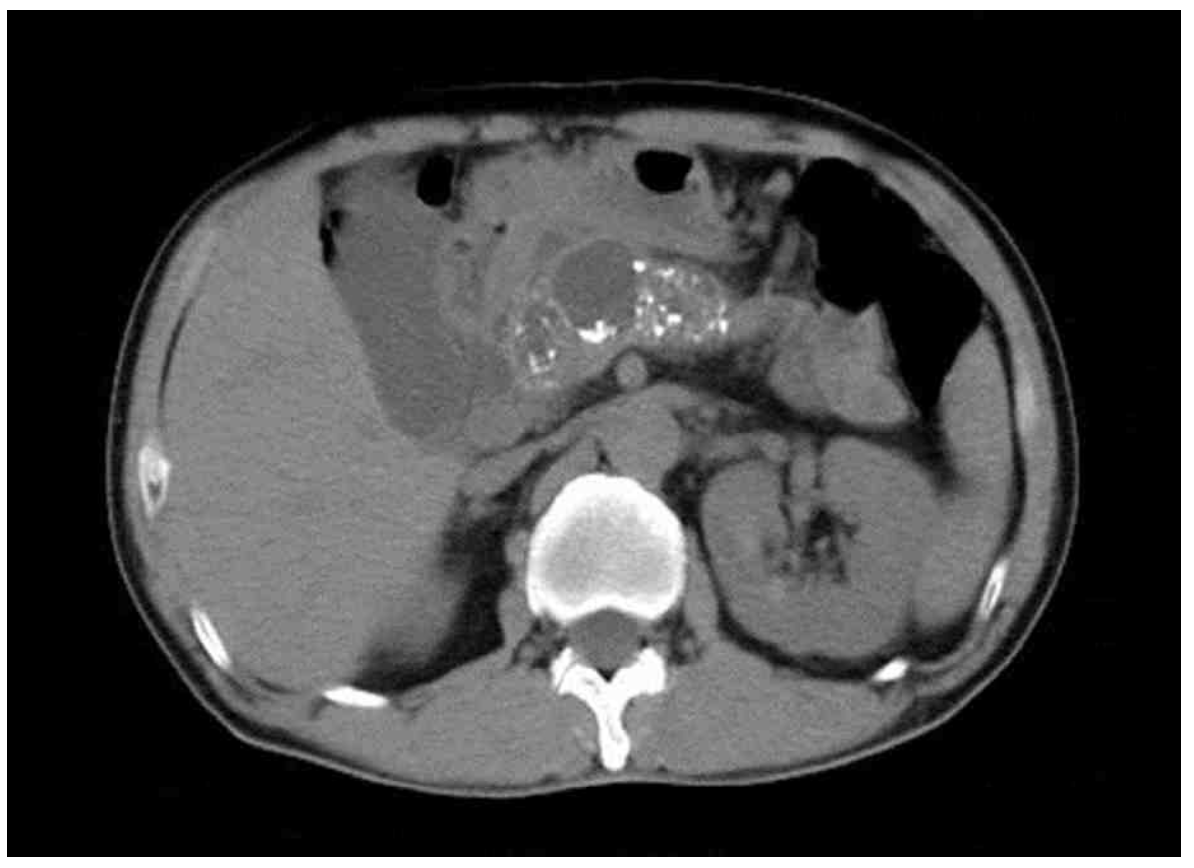

61세 남자가 2년 전부터 종종 윗배가 아프다고 병원에 왔다. 1개월 전부터 대변을 보면 변기물에 기름이 뜬다고 한다. 40갑•년의 흡연자이다. 30세 이후로 매일 소주 한 병을 마신다고 한다. 혈압 130/90 mmHg, 맥박 80회/분, 호흡 18회/분, 체온 36.7°C이다. 배 청진에서 장음은 약간 항진되어 들린다. 배에 압통과 반동압통은 없다. 혈액검사 결과는 다음과 같다. 복부 컴퓨터단층촬영 사진이다. 치료는?

CT: Pancreatic calcification

• 혈액검사 결과 mild ALP elevation, Hb 감소 외 특이사항은 확인되지 않으나, 복부 CT상 pancreatic calcification이 저명하게 관찰되는데, 이는 만성 췌장염의 전형적인 영상소견 중 하나이다.

• 따라서, 임상증상 및 CT 소견을 종합할 때 만성 췌장염(chronic pancreatitis)로 진단 가능하다.